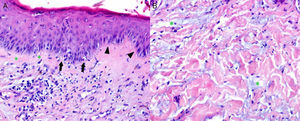

The laboratory tests included RF (83.1IU/mL), ANA (1/2560 speckled pattern) and positive anti-Ro/SSA and anti-La/SSB. The skin biopsy was compatible with LE and EM (Fig. 2A and B).

(A) Epidermis with vacuolar degeneration of the basal cells (asterisks), isolated necrotic keratinocytes (arrows) and associated lymphocyte infiltrate. The image shows the verticality of the basal cells (arrowheads), a histological feature associated with erythema multiforme. Infiltrated lymphocytes and melanophages in papillary dermis. (B) Reticular dermis with interstitial mucin (asterisks).